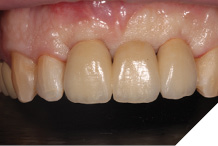

The definitive bridge was fitted and torqued in situ uneventfully after such excellent healing of the provisional bridge (Figs. 31-37).

Final result

The definitive bridge has integrated well and both hard and soft tissue healing has gone well and very predictably. The chosen biomaterials have integrated well and healed exactly how we would expect them to. The patient was very happy with the aesthetic result especially when we consider what he had been used to preoperatively. The function and phonetics met the patient’s expectations and overall, we were all very happy with the result.